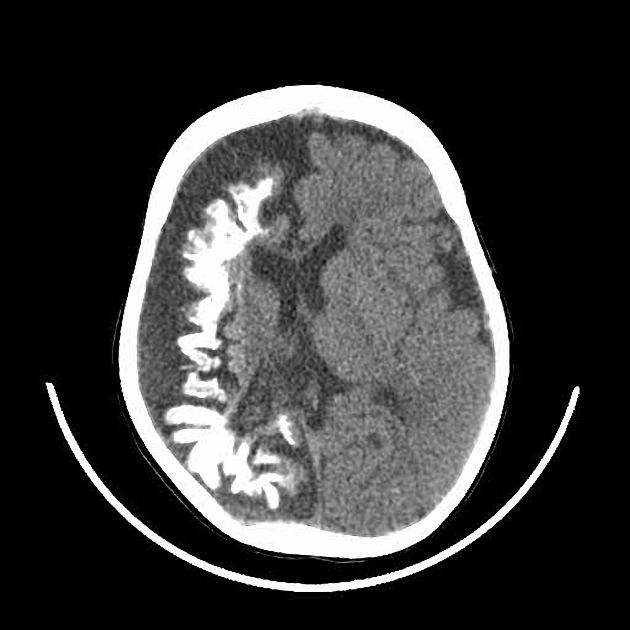

A 10-year-old boy is brought to a family physician by his mother with a history of recurrent headaches. The headaches are moderate-to-severe in intensity, unilateral, mostly affecting the left side, and pulsatile in nature. Past medical history is significant for mild intellectual disability and complex partial seizures that sometimes progress to secondary generalized seizures. He was adopted at the age of 7 days. His birth history and family history are not available. His developmental milestones were slightly delayed. There is no history of fever or head trauma. His vital signs are within normal limits. His height and weight are at the 67th and 54th percentile for his age. Physical examination reveals an area of bluish discoloration on his left eyelid and cheek. The rest of the examination is within normal limits. A computed tomography (CT) scan of his head is shown in the exhibit. Which of the following additional clinical findings is most likely to be present?